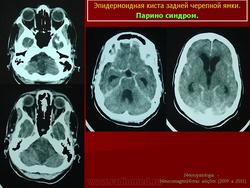

Эпидермоидные кисты задней черепной ямки

С 1985 по 2000 г.г. в НИИ нейрохирургии им. Н.Н. Бурденко обследовано и оперировано 78 больных с эпидермоидными кистами задней черепной ямки. Изучен клинический симптомокомплекс и КТ, МРТ картина эпидермоидных кист задней черепной ямки.

Эпидермоидная киста